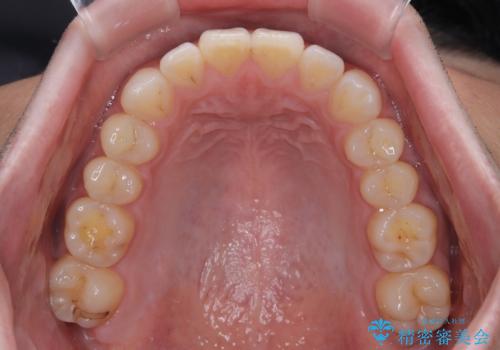

一年と数か月で矯正を終えることができました。

下顎前歯部には後戻り防止のワイヤーを装着しています。

- 上下顎歯列のデコボコを改善したいとのことで来院された患者様です。